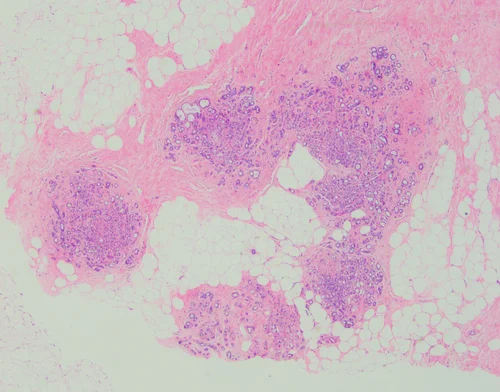

Microglandular Adenosis

Microglandular adenosis is an uncommon proliferative glandular lesion that is important to recognize because it mimics carcinoma clinically and pathologically.

Microglandular adenosis is characterized by an infiltrative, nonlobulocentric proliferation of relatively uniform, small glands within the stroma and adipose tissue.

Microglandular adenosis is composed of small round glands that are lined by a single layer of flat-to-cuboidal epithelial cells. The glands lack an outer myoepithelial cell layer. They often have an eosinophilic, PAS+ Diastase resistant secretory material within the lumina.